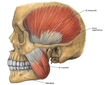

Çiğneme kasları, ağız içinde bulunan ve yiyeceklerin mekanik olarak parçalanarak sindirim sürecine hazırlanmasında önemli rol oynayan kas gruplarıdır. Bu kaslar, yalnızca yiyeceklerin parçalanmasında değil, aynı zamanda konuşma, yutma ve yüz ifadelerinin oluşumunda da kritik bir işlev üstlenmektedir. Çiğneme Kaslarının Anatomik Yapısı Çiğneme kasları, başın yan tarafında yer alan birkaç ana kas grubundan oluşur. Bu kaslar arasında en önemli olanları şunlardır:

Bu kaslar, çiğneme hareketlerini gerçekleştirirken, alt çenenin yukarı, aşağı ve yan hareketlerini sağlamaktadır. Çiğneme Kaslarının Fonksiyonları Çiğneme kasları, aşağıdaki temel fonksiyonları yerine getirir: